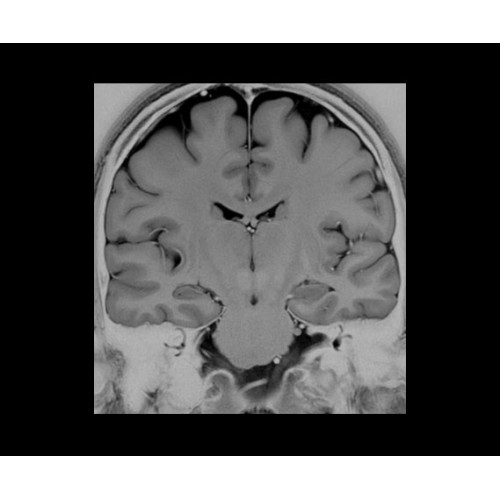

• NeuroWorks — универсальное решение для визуализации анатомии головного мозга, позвоночника, сосудов и периферических нервов с четкой дифференциацией тканей.

Поле обзора 50x50x50 см и апертура шириной 70 см позволят достоверно визуализировать сложные анатомические области для пациентов с крупным телосложением, например, плечи и бедра. Феноменальная однородность системы SIGNA Architect обеспечивает наиболее широкое поле обзора с улучшенными характеристиками градиентов. Ничто не останется незамеченным.